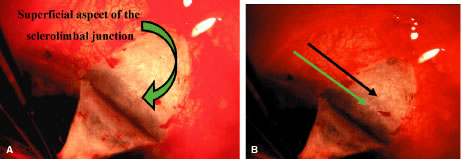

is not within the tissue to be cut by the scissors. Tenon's capsule, with its conjunctiva, is spread anteriorly over the

cornea to give the best view possible of the corneal scleral sulcus. In

almost all instances, there is a thin layer of episclera remaining. This

layer is grasped and elevated forcibly, permitting development

of a 2 × 2-mm buttonhole, through which the bare sclera is easily

visible. This episcleral tissue is markedly adherent. The buttonhole

should be extended approximately 5 mm temporally and laterally. The

forceps are used to grasp the edge of this deep episcleral tissue, and

pull it anteriorly and inferiorly, so the surgeon can clean down to bare

sclera anteriorly to the corneoscleral sulcus. The sulcus is not readily

visible until the episcleral tissue has been reflected from it. In

fact, it probably is the single most important landmark with regard

to filtration surgery. As seen in Figure 4, the conjunctiva inserts just anteriorly to the corneoscleral sulcus. Dissection

with acute or chronic primary angle-closure glaucoma. We prefer to clean the conjunctiva meticulously until no fibers are crossing

the corneoscleral sulcus. The most effective method is to use a

no. 67 Beaver blade held at a 45-degree angle from the direction of the

incision. Only the pointed tip is used to cut the tissue (see Fig. 13A). The dissection is continued anteriorly until the conjunctiva can no

longer be cleaned further anteriorly. The corneoscleral sulcus should

be free of fibers for a width of approximately 4 to 5 mm. Partial cleaning of the area posterior to the corneoscleral sulcus can